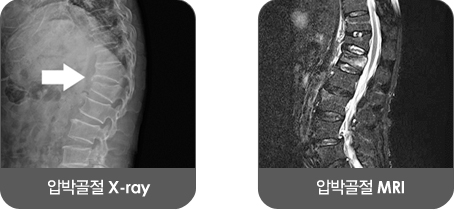

후관절통, 요추협착증과 함께 노인성 요통의 대표적인 원인 중에 하나가 압박골절입니다.

흔히 골절이라고 하면 뼈가 부러지거나 금이 가는 상태를 말하지만 척추의 압박골절은 서로 간격을 유지하며 맞물려 있어야 할 척추뼈가 납작하게 내려앉는 증상을 가리킵니다.

압박골절의 흔한 원인중의 하나는 골다공증입니다. 골밀도가 정상인 사람은 강한 충격에도 타박상을 입을 뿐 뼈가 부러지는 예는 드문데 골다공증이 있으면 가볍게 엉덩방아만 찧어도 척추에 쉽게 압박골절이 일어납니다. 골다공증은 뼈의 노화가 주요 원인이므로 압박골절 환자도 대부분 60~70대 이상 노인층입니다. 골다공증에 걸릴 위험이 높은 경우